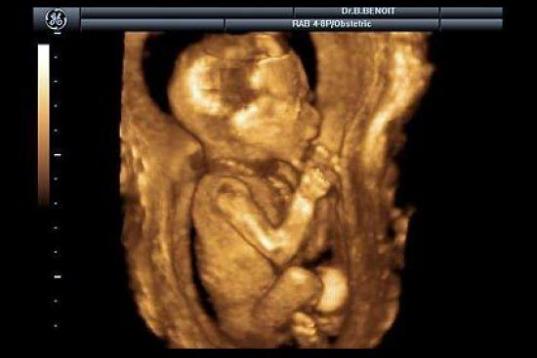

En esta galería puedes ver en fotos como es el desarrollo de un feto de semana en semana:

Desarrollo del feto, en fotos